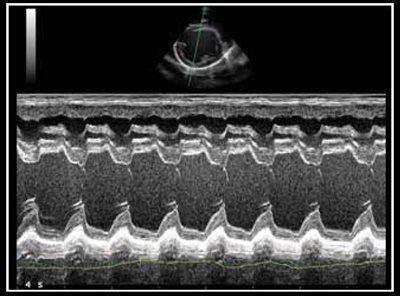

Photo 10 - Dilatation ventriculaire gauche.